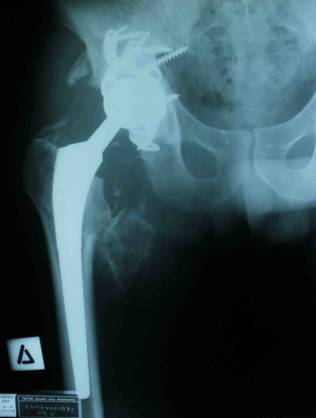

definite treatment in the right hip was applied cementless total

hip arthroplasty with metal cage as posterior wall support.

[Fig. 4]

Fig.4: A total hip Arthroplasty was applied with metal

cage for posterior wall support.